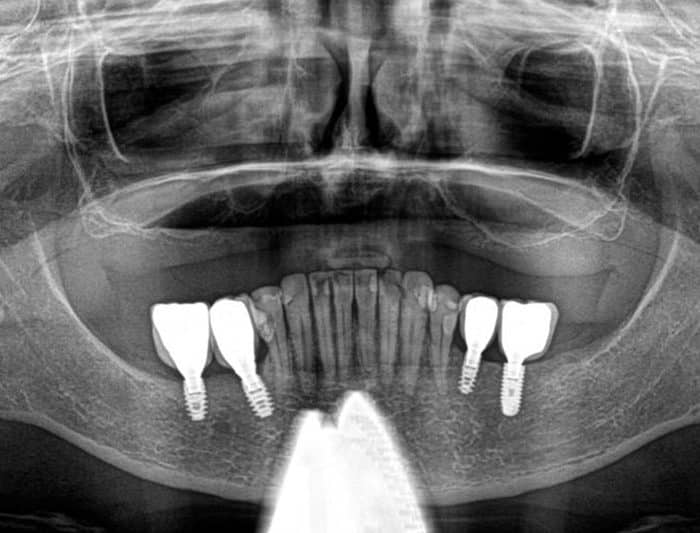

Design My Implants uses CT scans to create tailored bone reconstruction systems. Our titanium parts are finely polished and treated for optimal bone bonding. We strategically place the device and screws for maximum durability. The screws are set in the densest bone areas for secure fixation. Our entire process emphasizes precision for lasting results.

Designed specifically for individuals with complete or partial tooth loss in the upper or lower jaw. Our subperiosteal implants offer a tailored solution to restore not just your smile but your confidence and quality of life.”

- Suitable for All Bone Types

Our subperiosteal implants are designed to adapt to any bone structure, making them suitable for a wide range of patients, regardless of their bone density or volume.